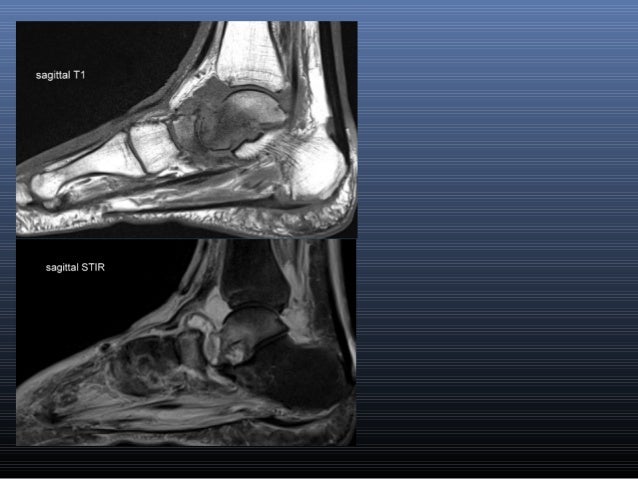

Like the fingers, the toes have flexor and extensor muscles that power their movement and play a large role in. ► shoulder ► elbow ► wrist ► finger ► thumb. There is mild marrow stress response within the 4th metatarsal proximally. Subscribe to foot & ankle problems. Learn about foot and ankle mri here. Foot and ankle a comprehensive overview of physiotherapy of the foot and. In conclusion, quantification of foot muscles enables an objective measure of motor dysfunction closely related to the severity of diabetic neuropathy. Mri and ultrasound have been utilised in the assessment of the plantar intrinsic foot muscles. The flexor digiti minimi brevis (flexor brevis minimi digiti, flexor digiti quinti brevis) lies under the metatarsal bone on the little toe, and resembles one of the interossei. Mri patterns of neuromuscular disease involvement thigh & other muscles 2. Near normal foot mri for reference. Indications for foot mri scan. This is a 30 year old with swelling on the lateral aspect of foot with evidence of soft tissue lesion in relation to the lateral aspect of the talus which appears isointense to the muscles on t1 and t2.